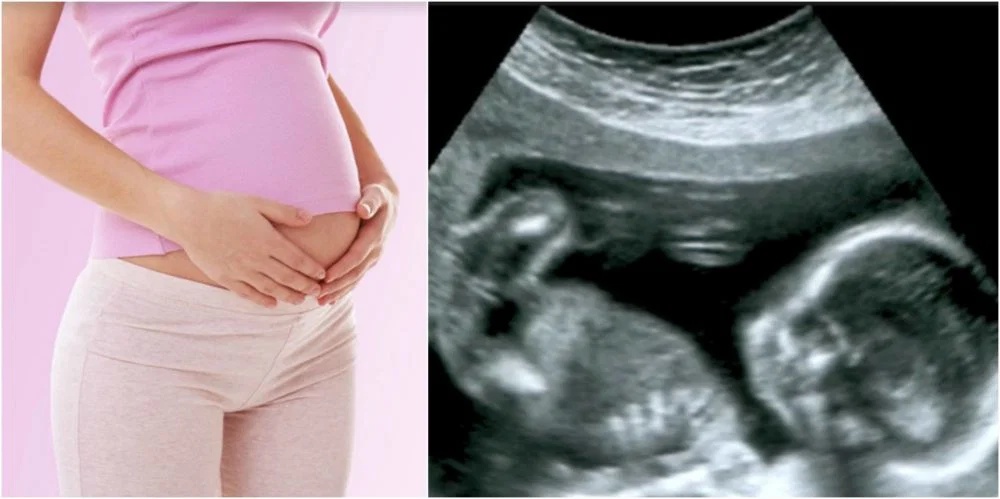

Xử phạt nghiêm khắc hành vi bói toán giới tính thai nhi từ 15 . 5 . 2026 - Ảnh 1.

Ảnh minh họa